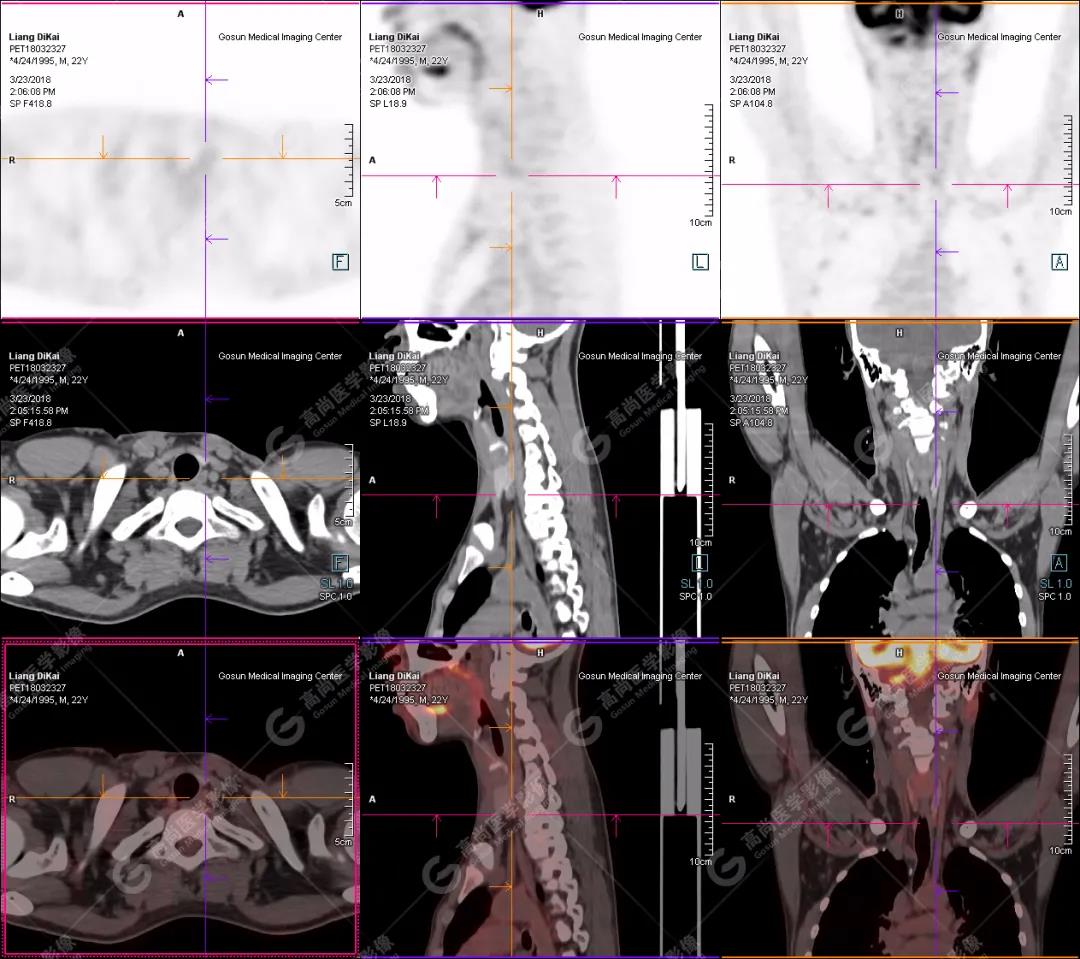

本中心PET/CT提示

1.右肘關(guān)節(jié)周圍、骶尾部皮下、雙側(cè)臀部、盆腔左側(cè)壁及左側(cè)大腿根部肌肉、肌間隙多發(fā)結(jié)節(jié)狀、片塊狀及不規(guī)則巨塊狀高密度鈣化灶,伴代謝不均勻輕度增高,考慮為鈣質(zhì)沉著癥;

2.甲狀腺雙葉后方多發(fā)(右2個,左1個)小結(jié)節(jié)狀軟組織影,部分代謝輕度增高,多考慮為甲狀旁腺腺瘤。